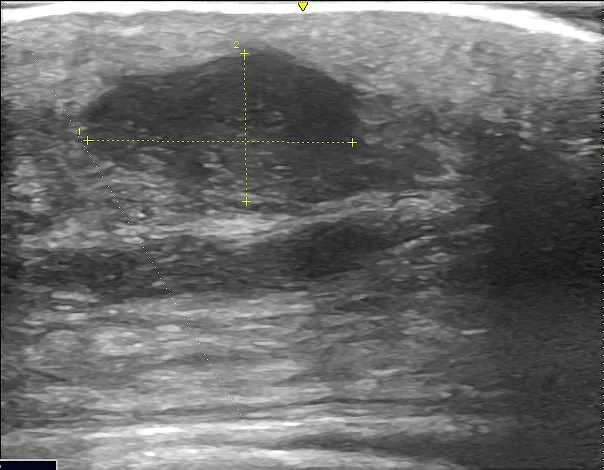

超音波検査では、粉瘤に特徴的な所見が確認され、炎症が強い状態であることが分かりました。

術前超音波検査